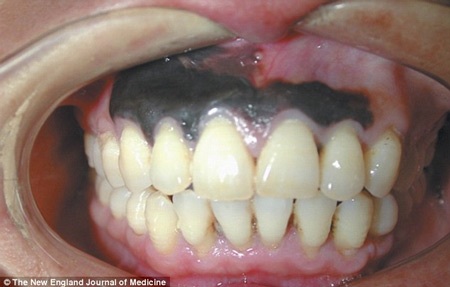

Bệnh nhân không hề cảm thấy đau đớn khi lợi chuyển dần sang màu đen. Và chỉ gần một tháng trở lại đây, khi sức khỏe của ông ngày càng trầm trọng, đi khám, ông mới biết mình bị ung thư da hắc tố.

Lợi chuyển màu đen và hoàn toàn không đau đớn

Khối u màu đen có diện tích bao trùm hầu như toàn bộ phần lợi trên của người đàn ông này.Theo Tạp chí Y khoa của Anh, vùng lợi bị đen khoảng 1,5x4cm và đây là ung thư da hắc tố, 1 dạng ung thư hiếm gặp, chiếm chưa tới 5% các trường hợp ung thư khác có liên quan đến melanocyte, tế bào sản sinh hắc sắc tố, có thể xuất hiện ở bề mặt niêm mạc của cơ thể, các khoang mũi, miệng, âm đạo, hậu môn và một số vị trí khác.